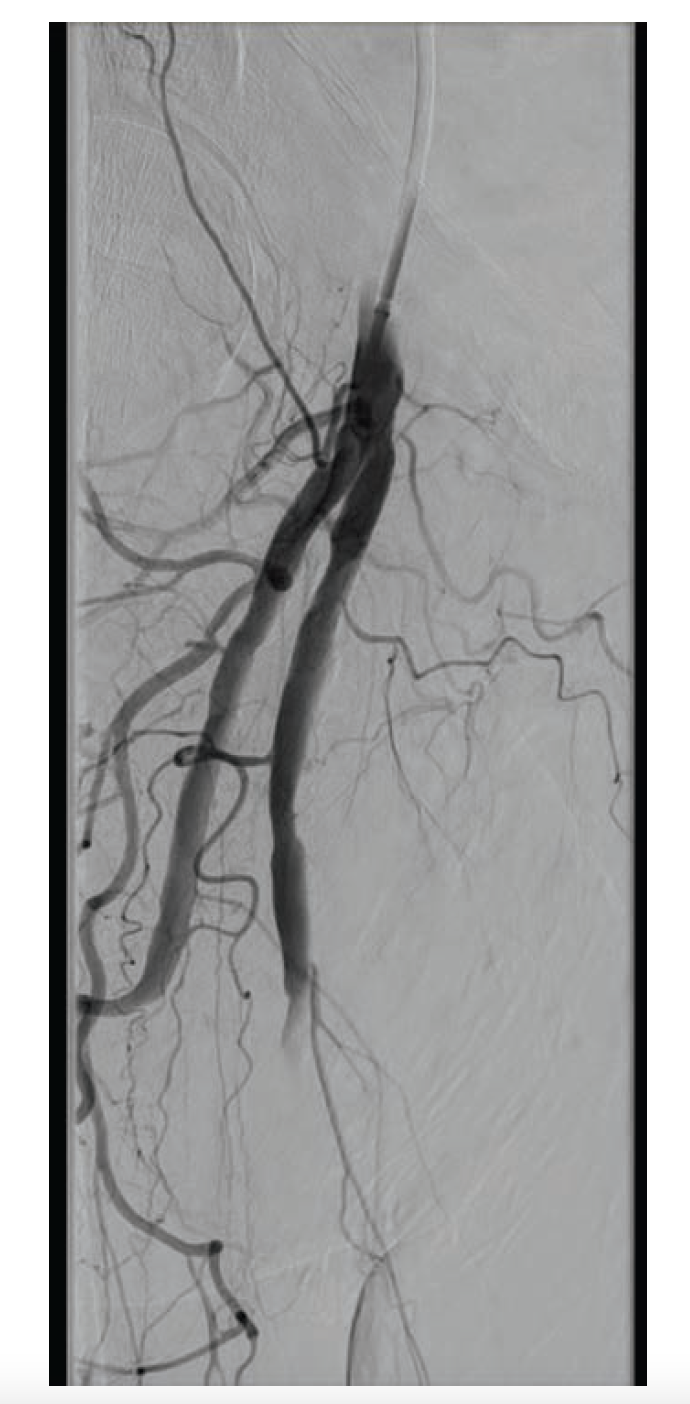

A 70-year-old man was referred for consideration of right lower extremity (RLE) intervention after initially presenting with resting ischemic pain and early tissue necrosis of the metatarsals, consistent with critical RLE ischemia. The patient was taken to the catheterization lab, where contralateral left common femoral artery (CFA) access was gained using a Micropuncture needle (Cook Medical) under ultrasound guidance. A 6F, 11 cm arterial sheath was placed into the artery over a guidewire. The right common iliac artery was engaged using a 5F internal mammary artery catheter; a 0.035" stiff-angled Glidewire (Terumo Interventional Systems) was then advanced to the right CFA. Peripheral angiography of the RLE was performed, demonstrating a total occlusion of the superficial femoral artery (SFA) as well as total occlusion of the popliteal artery and all three infrapopliteal vessels (Figure 1 and Figure 2). The 6F sheath was then exchanged over the Glidewire for a 6F, 45 cm sheath. At this time, anticoagulation was initiated with intravenous unfractionated heparin at 80 units/kg to achieve an activated clotting time (ACT) > 250 seconds.